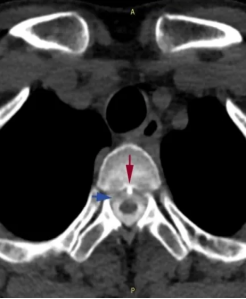

小江的脊柱磁共振检查可见第1、2胸椎之间有“骨刺”形成(红箭头)刺破硬脊髓膜,造成脑脊液外漏(蓝箭头)